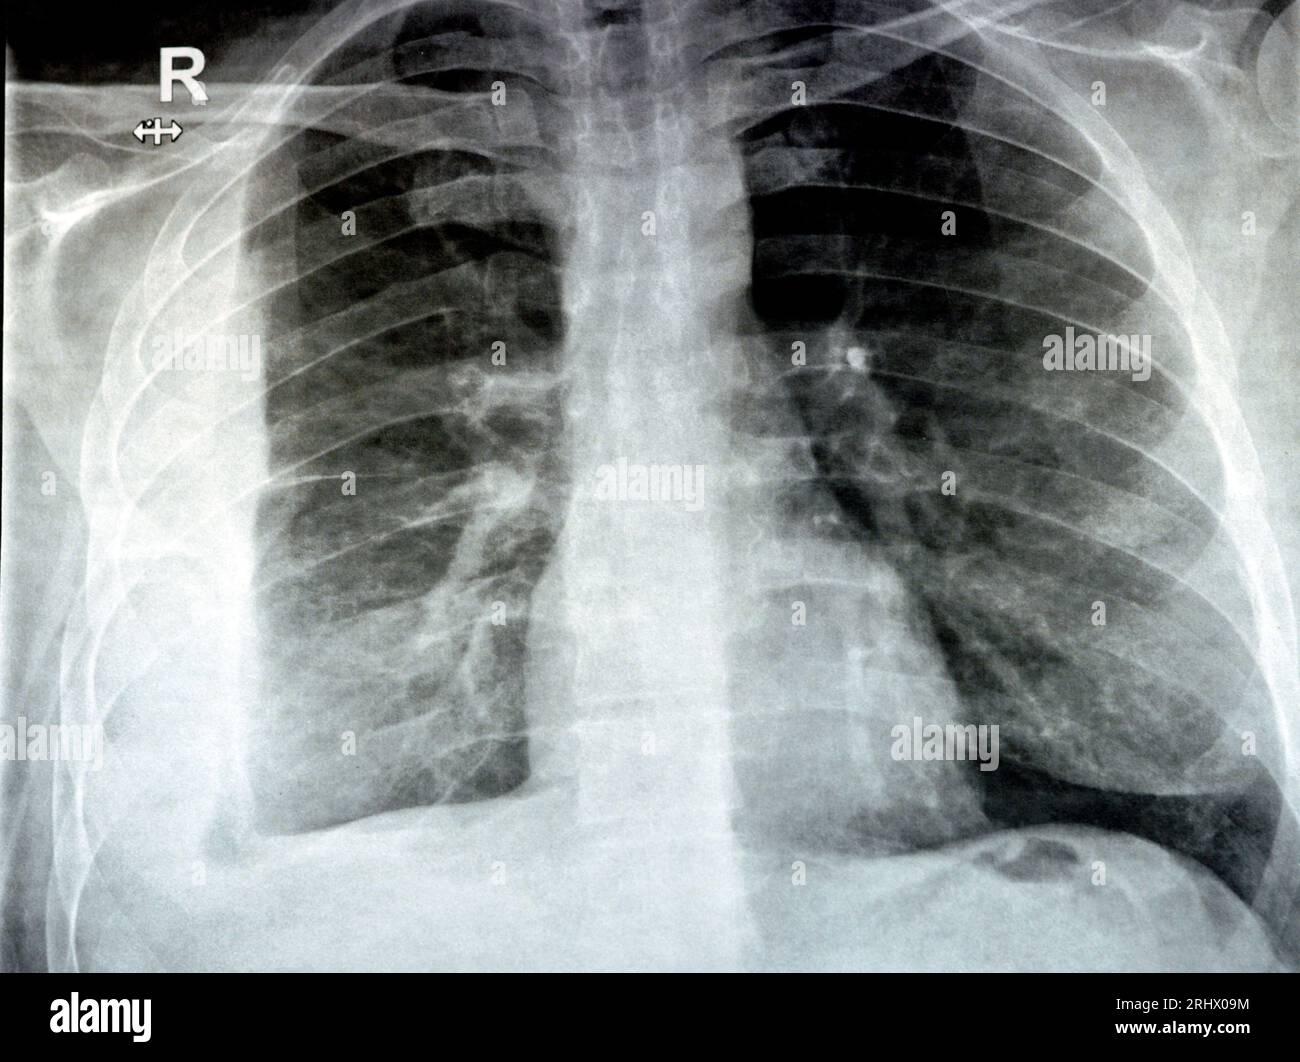

From www.alamy.com

Plain X ray for a patient with aspiration pneumonia right lung, empyema Rattling Chest Pneumonia — the doctor does this to check for what is called “rales,” which are small clicking, bubbling or rattling sounds in the. The air sacs may fill with fluid or pus (purulent material), causing cough. — wheezing is the shrill, coarse whistling or rattling sound your breath makes when your airway is partially blocked or narrowed. The air. Rattling Chest Pneumonia.